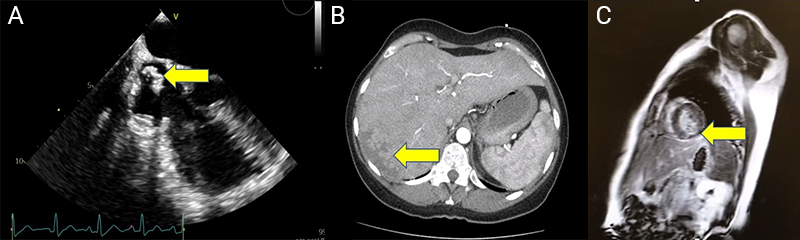

Thoracoabdominal CT excluded pulmonary embolism, but revealed findings suggestive of hepatic infarction, and pancreatic calcifications consistent with chronic pancreatitis (figure 2B). Coronary angiography was subsequently performed and showed no obstructive coronary artery disease. Given the suspicion of embolic phenomena, transoesophageal echocardiography was performed to further evaluate for intracardiac sources of embolism. It identified a mass in the superior vena cava extending into the right atrium (figure 2A). Cardiac MRI demonstrated late gadolinium enhancement (subendocardial) in the basal segments of the inferolateral and inferoseptal walls (figure 2C), consistent with an embolic event.